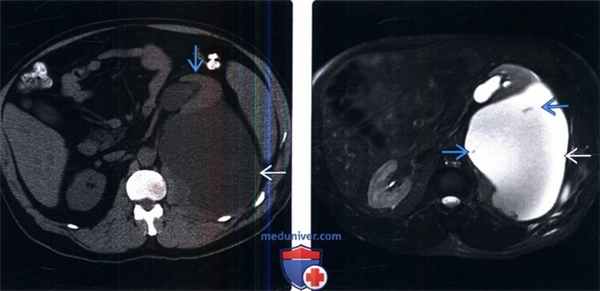

(Слева) КТ без контрастирования после частичной нефрэктомии, аксиальный срез. Уринома больших размеров гомогенной водной плотности, окруженная капсулой. Обратите внимание на смещение левой почки кпереди и гидронефроз, вследствие эффекта сдавливания.

(Справа) МРТ, Т2-ВИ, режим подавления сигнала от жира, аксиальный срез: гомогенная, гиперинтенсивная уринома: визуализируются несколько тонких перегородок.